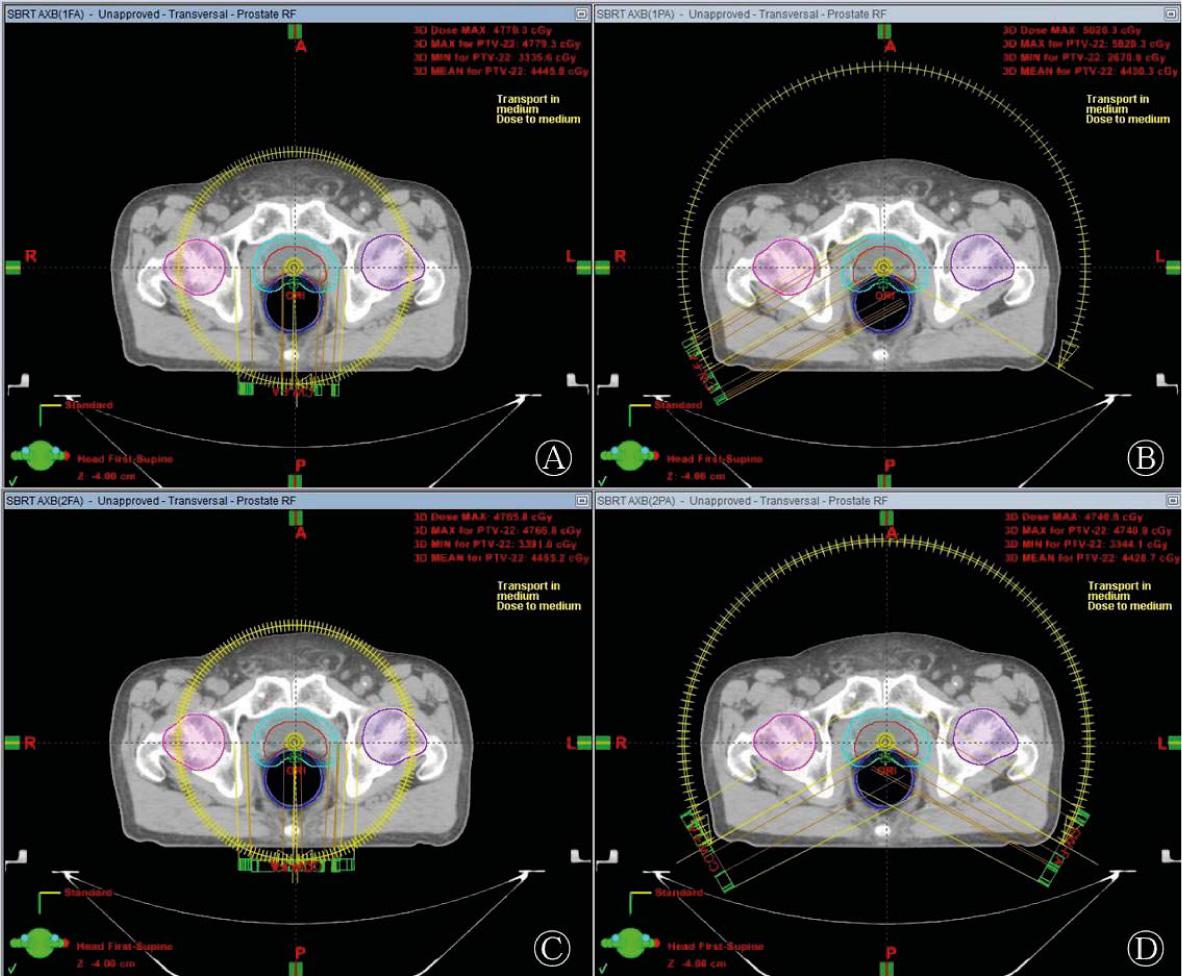

Average monitor unit and delivery time for prostate SBRT-VMAT plans using four arc arrangements_

| Beams | 1FA (Mean ± SD) | 1PA (Mean ± SD) | 2FA (Mean ± SD) | 2PA (Mean ± SD) |

|---|---|---|---|---|

| MU | 1575±63 | 1627±56 | 1646±97 | 1660±98 |

| Delivery time (min) | 1.01±0.02 | 0.69±0.01 | 2.00±0.01 | 1.36±0.02 |